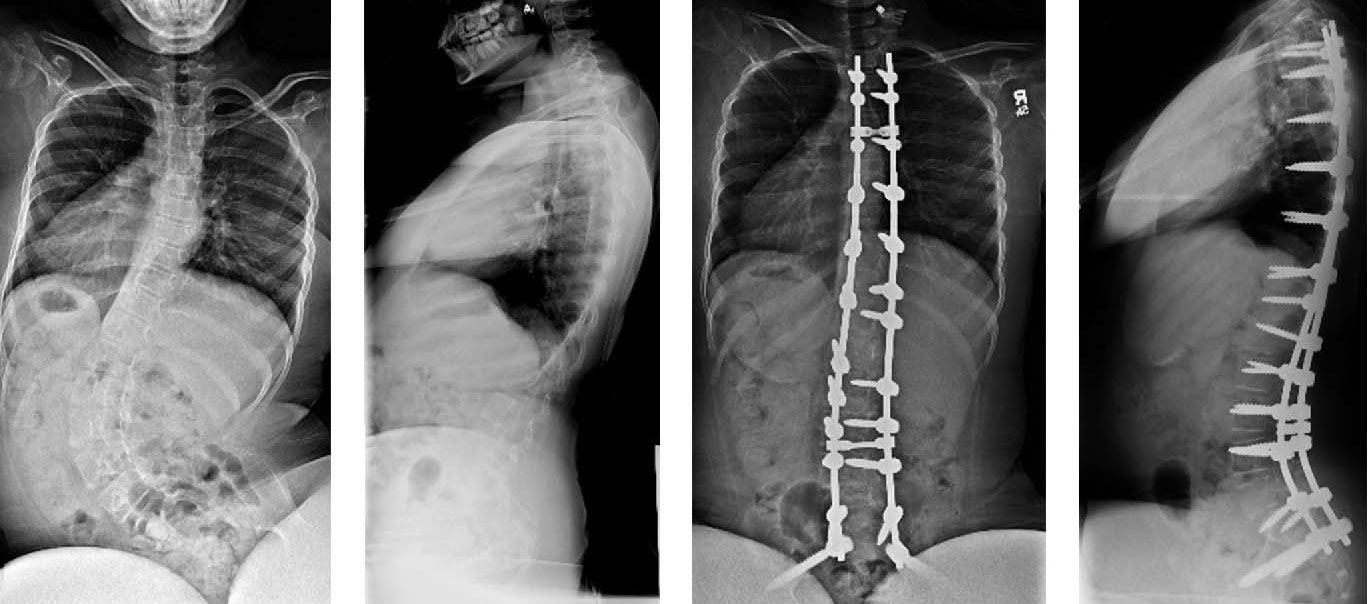

x-rays of large spinal curve and fusion

(Left) X-rays of a 12-year-old girl with type 2 spinal muscular atrophy show a large 93-degree spinal curve. (Right) The spine has been stabilized by two rods and multiple screws, bringing the curve to a more normal alignment.

Reproduced from Mesfin A, Sonseller P, Leet A. Spinal Muscular Atrophy: Manifestations and Management. J Am Acad Orthop Surg. 2012; 20(6):393-401. doi: 10.5435/JAAOS-20-06-393